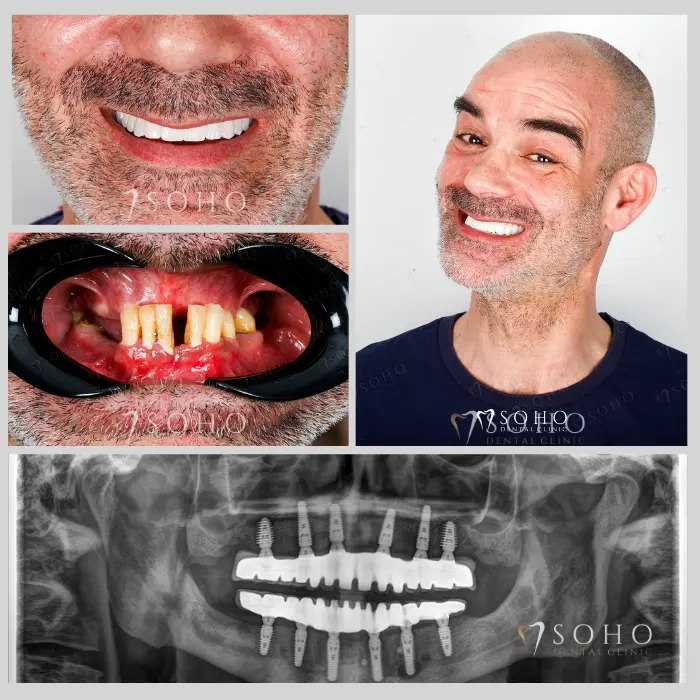

Real Patients. Real Smiles.

Explore the journey of our international patients through authentic visuals, elegant transformations, and moments captured inside Soho Dental Clinic. Let their stories inspire your own.

From First Visit to Final Smile.

Explore real patient stories captured in every transformation. These are more than smiles — they are renewed confidence, achieved with care and precision at Soho Dental Clinic.